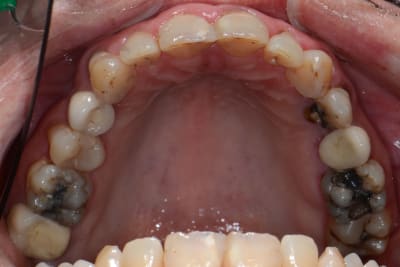

Nouvelle patiente 60 ans, pas de tabac, pas d'habitudes alimentaires prédisposantes mais syndrôme sec, très peu de salivation et ce depuis 2 ans.

A l'examen clinique, caries de collets typiques, la 45 a du être dévitalisée. Les caries sont plus importantes cliniquement que radiologiquement. Par ex les incisives mand étaient presque intégralement cariées en linguale (?).

Je lui ai fais un bilan et ai décidé de soigner les caries de collet au CVI (GC Equia forte). La 24 et 45 seront couronnées.

Le souci est que malgré la fluoration (flucaril bi-fluoré), motiv à l'hygiène ca progresse quand même.